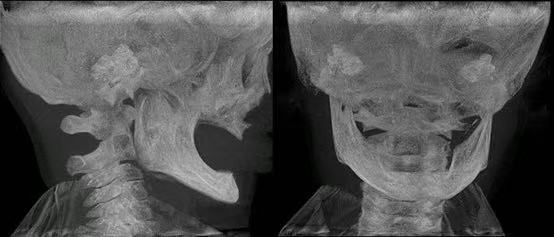

CBCT显示其颌骨发育严重不足。

CBCT显示,乳牙胚和恒牙胚缺如,其上下颌骨发育短小,牙槽骨厚度、高度严重不足,最薄处仅1~2毫米,“如纸一般菲薄”。

与临床常见因牙齿早失导致骨吸收的无牙颌老人不同,HED患儿的颌骨从未经历正常发育过程,骨量基础更为薄弱。这一结构缺陷,不仅使全口义齿固位极为困难,更意味着未来成年后可能不具备接受种植牙手术的解剖条件。